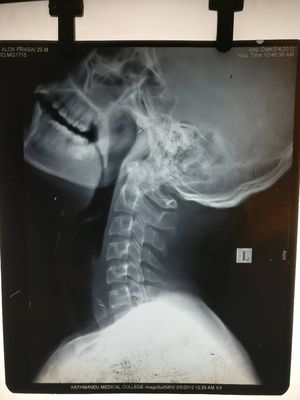

X-ray soft tissue neck lateral view

Neck

Esophagus

Foreign Body